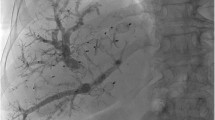

Major hepatic resection in HCC patients is often more challenging than for other hepatic malignancies due to the underlying liver disease or cirrhosis, which are associated with a higher risk of hepatic failure.[31] Compared to PVE in healthy livers, the degree of PVE-triggered hypertrophy in chronic liver disease is less predictable and PVE might theoretically induce a compensatory increase in hepatic arterial flow in the embolized segments [32]. Therefore, sequential transarterial chemoembolization (TACE) and PVE was proposed to control HCC, thereby buying time to augment liver volume (Fig. 3). For TACE, selective catheterization of the right hepatic artery is performed, then chemotherapy and an emulsion of iodized oil (e.g., lipiodol) is infused into the selected feeding artery. Afterwards, embolization with microspheres (e.g., absorbable gelatin sponge particles) is performed until arterial stasis is achieved (Fig. 4). TACE has antitumor effects by occluding tumor feeding vessels and showed promising results in HCC patients with chronic liver disease with a tumor response in half of the patients [33,34,35,36]. Evaluating the volumetric changes, different studies showed that sequential TACE and PVE induced even a greater hypertrophy in the non-embolized liver than PVE alone (Table 1) [34, 38, 39]. The time interval from TACE to PVE was 30 days (range 9–120 days) and from PVE to surgery 28 days (range 21–45 days) in a systematic review [40]. In retrospective studies, TACE + PVE led to a greater hypertrophy [34, 35, 38, 39] with improved overall survival (OS) [35, 39] and disease-free survival (DFS) [34, 35, 38, 39] as compared to PVE alone. However, the advantages of TACE need to be carefully balanced against its adverse events. Detoriating liver function, ischemic cholangitis, and intrahepatic abscess have been repeatedly reported [33, 37, 41]. On the other hand, failure to achieve sufficient hypertrophy after TACE and PVE indicates an impaired capacity of the liver to regenerate in patients with chronic liver disease. This feature can be used as “dynamic” liver function test to identify patients who are eligible for surgery.

Clinical case of transarterial chemoembolization and sequential portal vein embolization (University of Zurich). This 69-year-old patient presented with a 7-cm hepatocellular carcinoma (HCC) in liver segments V/VIII and an alpha-fetoprotein (AFP) of 42.649 μg/l (A/B). No portal hypertension or liver cirrhosis was present. For a right hemihepatectomy, a sFLR of 27% was calculated. Since the indocyanine green (ICG) test showed impaired liver function with a plasma disappearance rate (PDR) of 12.1%/min (normal value >18%/min) and ICG retention rate (R15) of 14.7% (normal value <10%), we opted for transarterial chemoembolization (C/D)followed by portal vein embolization 2 weeks later (E/F). After the successful embolization, the AFP dropped to 209 μg/l and the sFLR increased to 39% (G/H). We then performed a right hemihepatectomy (I/J). Three months postoperatively, the patient is tumor-free and in a good general condition